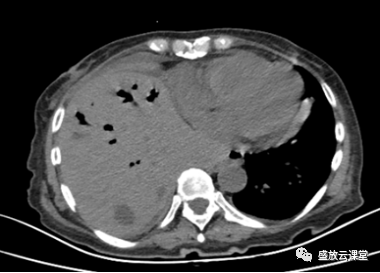

【病例】肺淋巴瘤(MALT)一例CT影像

【病例】肺淋巴瘤(MALT)一例CT影像-1

【病例】肺淋巴瘤(MALT)一例CT影像-1 【病例】肺淋巴瘤(MALT)一例CT影像-2